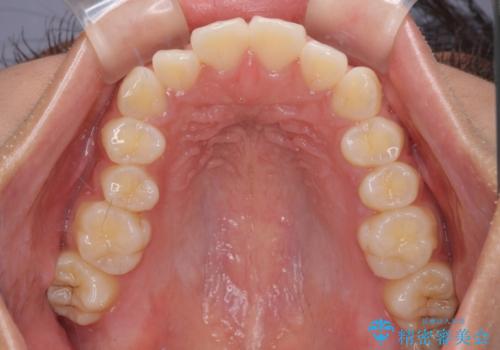

- 出っ歯と口の閉じにくさ、デコボコを気にして来院された患者様です。

口元の突出感を改善するため、上下左右第一小臼歯4本の抜歯を行い、ワイヤー装置による矯正治療を行うこととしました。

舌の突出癖により上下前歯は非接触であり、非常に前方に飛び出している状態でした。

舌のトレーニングをしっかりと行っていただき、口の閉じやすい歯並びに仕上げることができました。